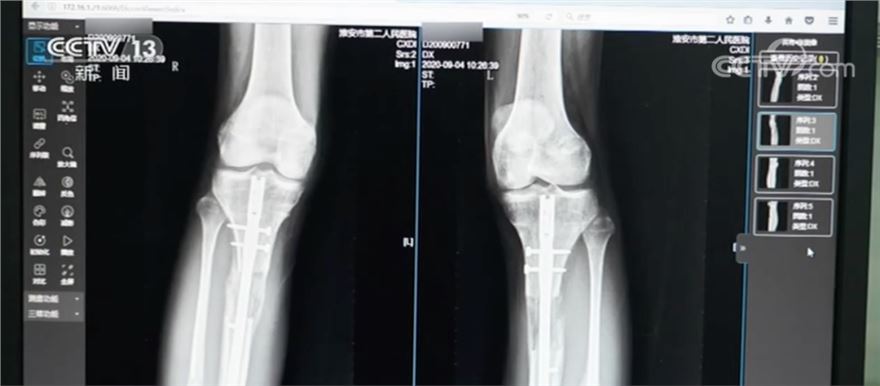

2020年,江苏省淮安市第二人民医院接诊了一名特殊患者。这名患者因为对自己的身高不满,在国外做了“断骨增高手术”,结果导致双腿严重感染无法行走,甚至面临终身残疾。

它是根据肢体组织在一定的力量刺激下可以再生的原理,把小腿或大腿的骨头“断开”,然后在体外安装具有牵伸作用的外固定支架,以每天不超过1毫米的速度,将肢体缓慢延长到满意的长度。

有骨科医生表示,在实施“断骨增高手术”时,外固定“增高器”的钢针要穿透患者的双腿,可能损伤腿部的血管、神经组织,造成感染,甚至引发骨髓炎,造成残疾。同时,“断骨增高手术”会造成血管损伤,严重的腿部血液供应障碍可能造成下肢组织坏死。